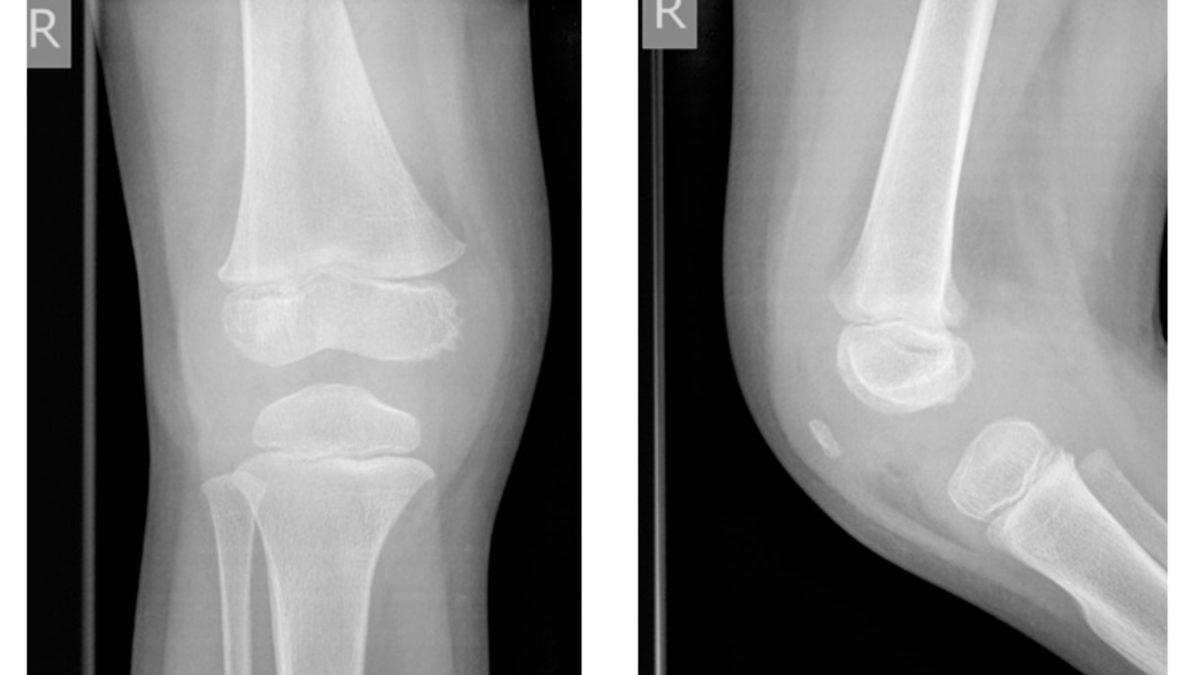

Bu nedenle bebeklerde aslında diz kapağı yok diyemeyiz. Diz kapakları var fakat gelişmeyi bekleyen bir kıkırdak yapıdalar. Hatta öyle ki kıkırdak yapıda oldukları için röntgende görünmezler.

Bir bebek emeklemeye başladığı zaman diz kapağında da gelişme başlıyor. 10 ve 12 yaşlarına gelindiğinde, diz kapağı tamamen kemiksi bir yapıya dönüşmüş oluyor. Yani kıkırdaktan kemiğe dönüşüm süreci yavaş ilerliyor ve uzun yıllar alıyor.